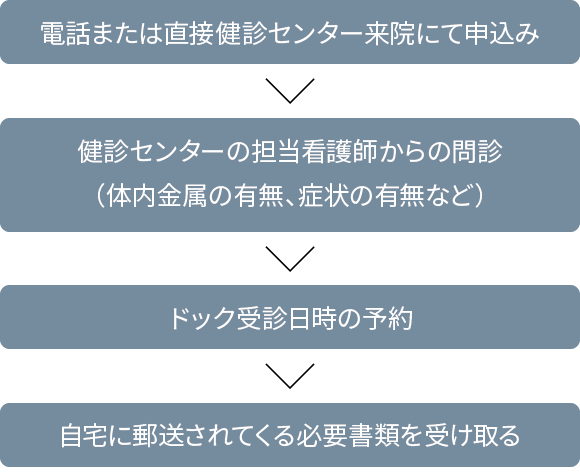

申し込みは下記にお電話いただくか、直接健診センターで受け付けております。

(申込み時に簡単な問診を行います)

電話:025-552-8835 健診センター 膵がん・胆道がんドック予約担当

(受付時間:午後1:00~午後4:00 *土日祝祭日を除く)